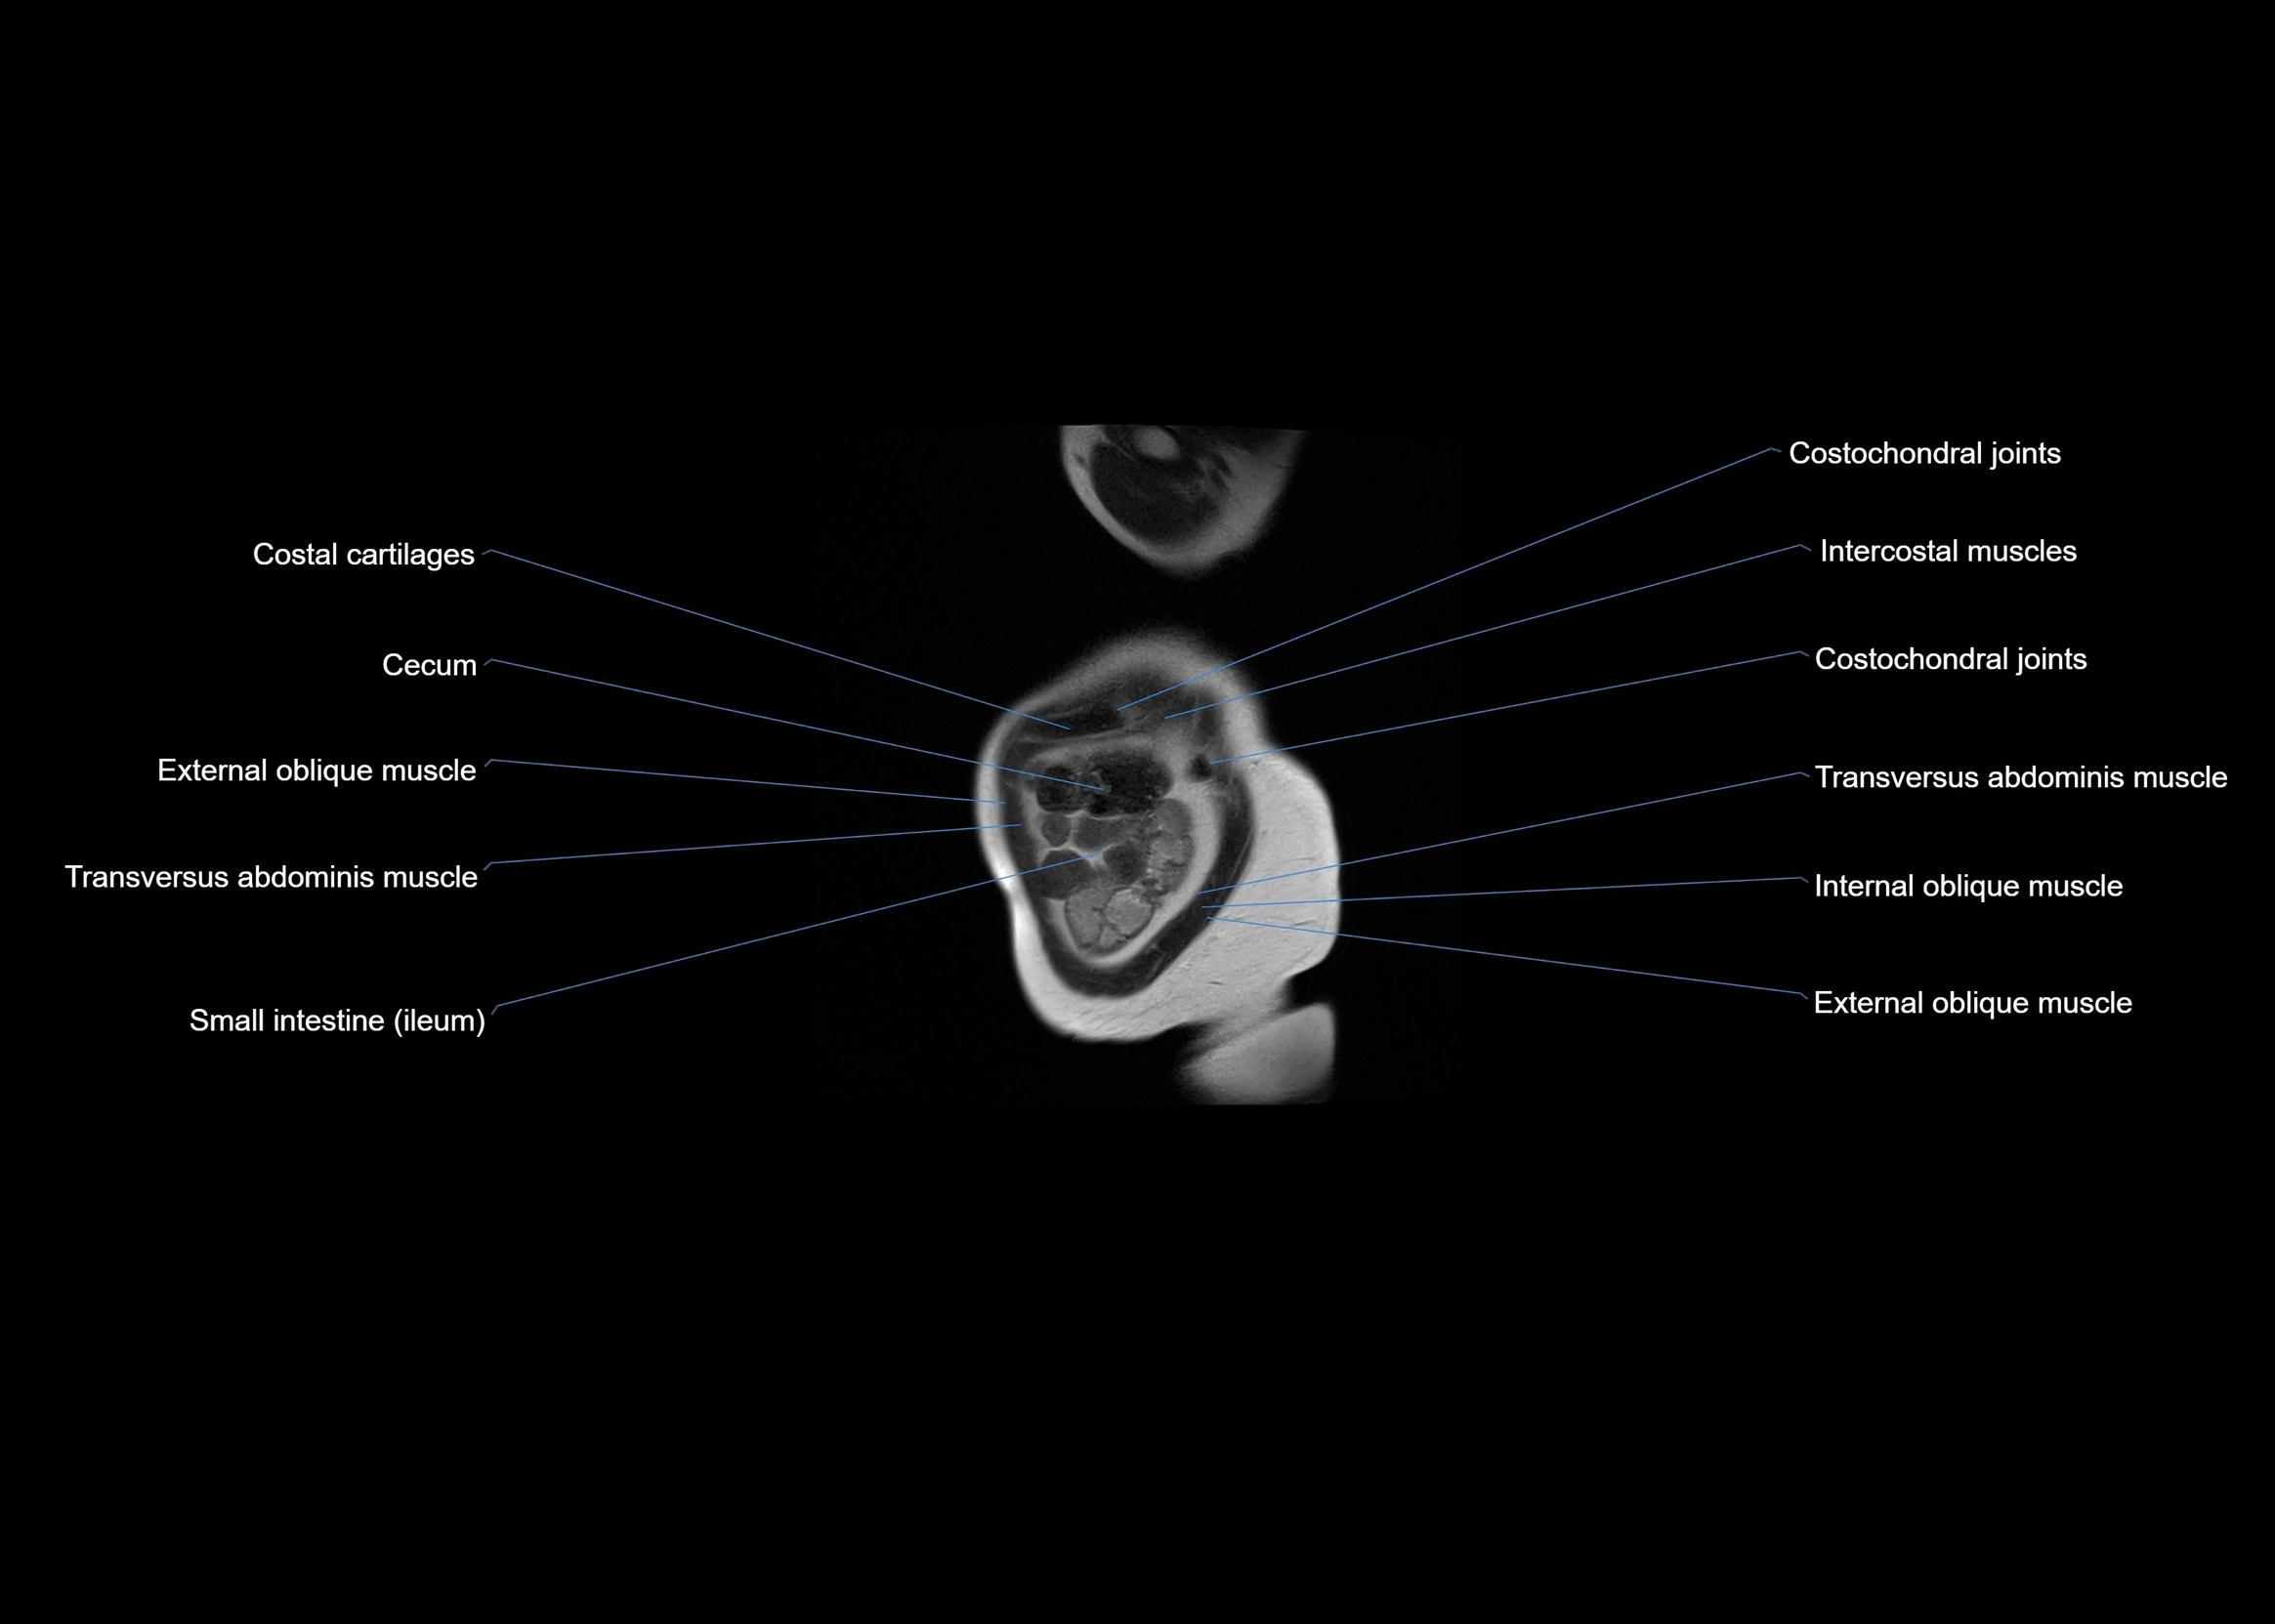

MRI images